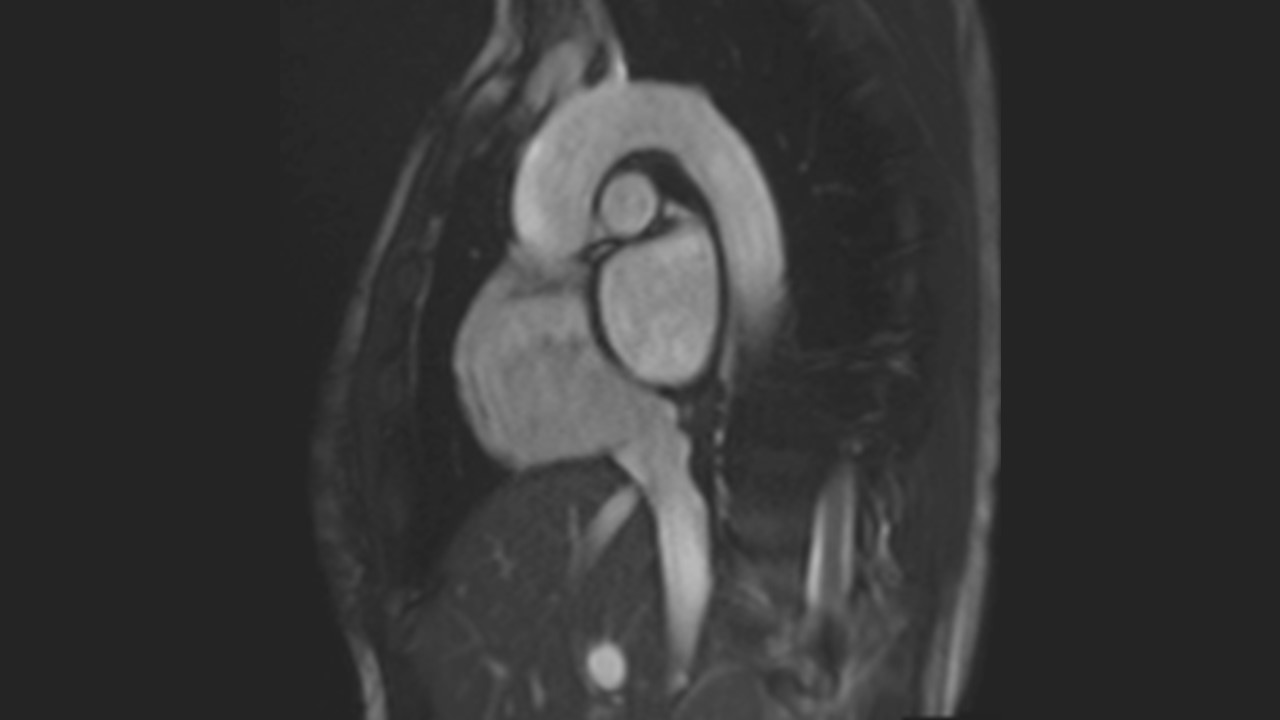

Aortic Arch Series